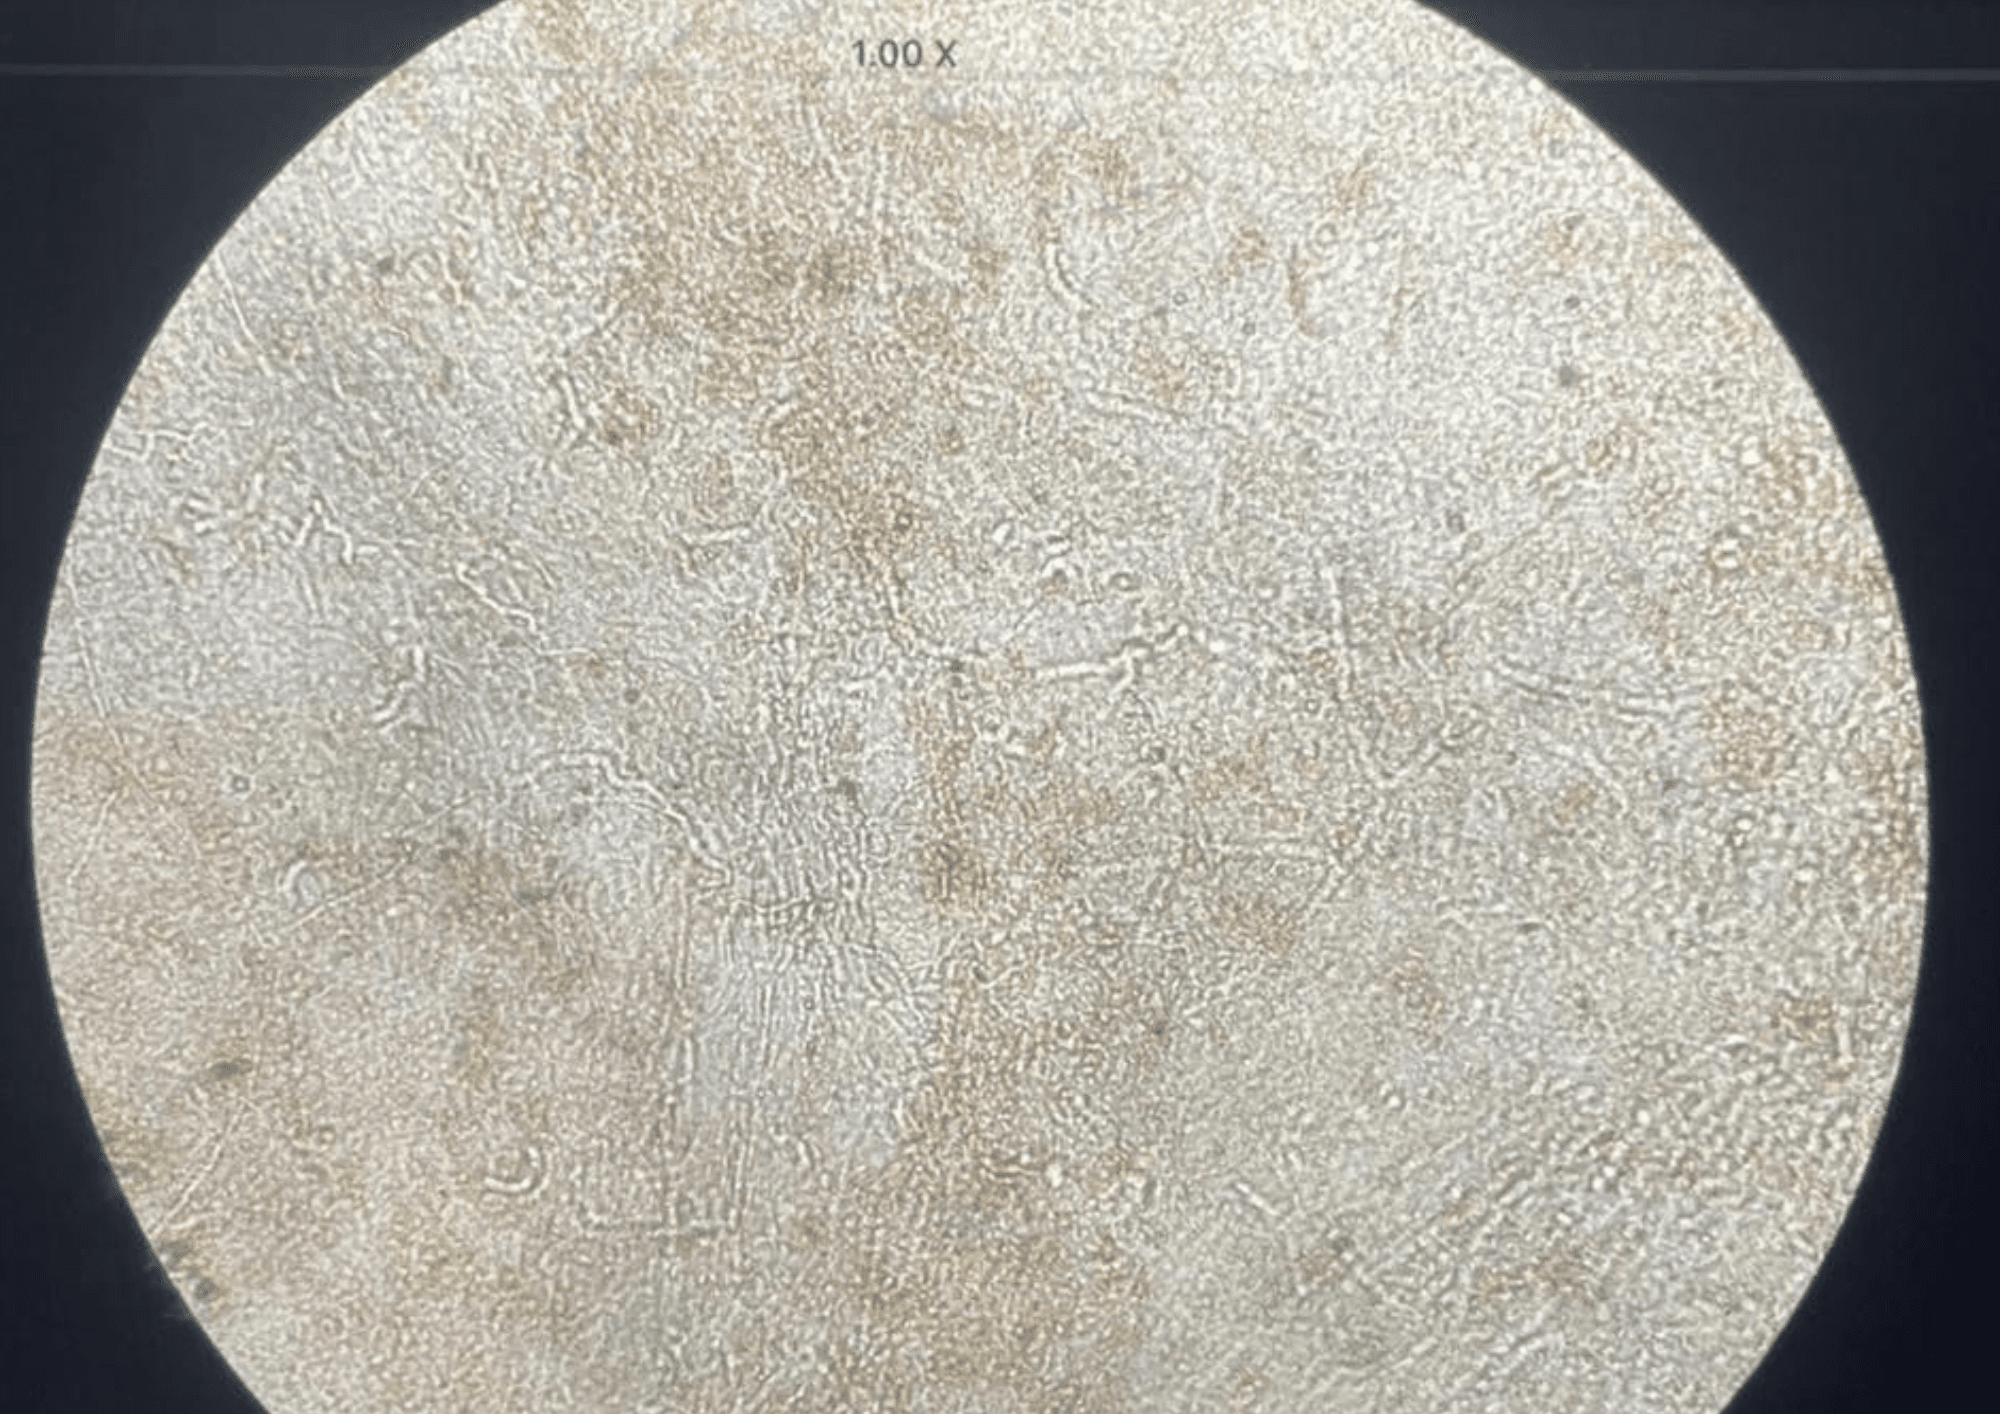

This photo shows widespread fungal infection of the skin affecting various body parts from a woman in Orissa.